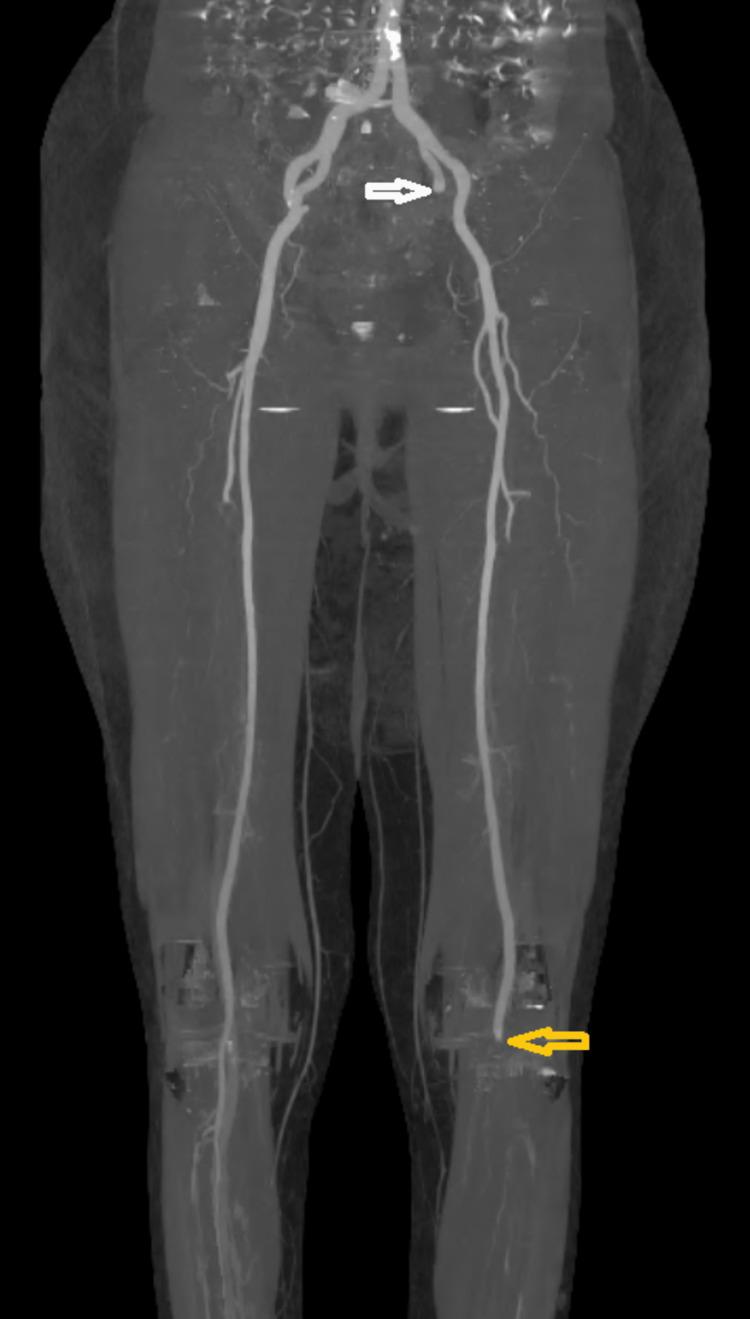

Introduction Severe acute respiratory syndrome coronavirus 2 (SARS-CoV-2) infection is currently known to lead to high rates of thrombotic complications. Of those, acute limb ischemia (ALI) was most frequently reported. Several case reports or case series had already described high mortality and amputation rates. The purpose of our study was to highlight the epidemiological, clinical, and management characteristics of coronavirus disease 2019 (COVID-19)-related ALI patients. Methods This was a monocentric, observational, and retrospective study. Records of all patients ≥18 years of age admitted with ALI and a confirmed diagnosis of COVID-19 infection between March 2020 and December 2021 were retrospectively examined. Data collected included demographics, co-morbidities, biological findings, COVID-19 pneumonia and ALI severity, anatomical location of arterial thromboembolism, treatments, and outcomes. Results During the study period, 22 patients with ALI infected with COVID-19 were evaluated. The median age was 67 years (45-88) and 18 (81.8%) were men. The main comorbidities were diabetes mellitus (36.4%), smoking (22.7%), and arterial hypertension (18.2%). All 22 patients were already diagnosed positive for SARS-CoV-2. The median duration between COVID-19 diagnosis and ALI symptom onset was six days (1-13 days). The computed tomography (CT) extent of pulmonary lesions was assessed according to the French Society of Chest Imaging. The ischemic syndrome was classified on Rutherford Stage IIA (30.4%) and IIB (43.5%). Regarding thrombotic locations, ALI had occurred essentially in the lower limbs (95% vs. 5%). A revascularization procedure was performed in 14 patients (63.6%) of the patients, and primary amputation was unavoidable in five patients (22.7%). Three patients (13.6%) did not undergo operative management, two because of their hemodynamic instability and one rejected surgery. We performed 23 revascularization procedures for 14 patients and three primary amputations. Thromboembolectomy (TE) was the technique of choice (92.8%). Below-the-knee (BTK) femoropopliteal bypass was performed in one patient. Selective tibial vessel thrombectomy was performed in four patients (28.6%). The mortality rate was 27.3%. Among survivors, two secondary amputations were needed with a limb salvage rate of 68.2%. Conclusion By the apparent end of the pandemic, our study further supports the increased risk of ALI in COVID-19-positive patients. Moreover, the results affirm the unfavorable outcomes highly impacted by rethrombosis, reinterventions, and consequently high rates of amputations and mortality.

结果 在研究期间,对22例感染COVID-19的ALI患者进行了评估。中位年龄为67岁(45 - 88岁),18例(81.8%)为男性。主要合并症为糖尿病(36.4%)、吸烟(22.7%)和动脉高血压(18.2%)。所有22例患者SARS-CoV-2检测均呈阳性。COVID-19诊断至ALI症状出现的中位时间为6天(1 - 13天)。根据法国胸部影像学会评估肺部病变的计算机断层扫描(CT)范围。缺血综合征根据卢瑟福分级为IIA期(30.4%)和IIB期(43.5%)。关于血栓形成部位,ALI主要发生在下肢(95%对5%)。14例患者(63.6%)接受了血运重建手术,5例患者(22.7%)不可避免地进行了一期截肢。3例患者(13.6%)未接受手术治疗,2例因血流动力学不稳定,1例拒绝手术。我们为14例患者进行了23次血运重建手术和3次一期截肢。血栓切除术(TE)是首选技术(92.8%)。1例患者进行了膝下股腘动脉旁路移植术。4例患者(28.6%)进行了选择性胫血管血栓切除术。死亡率为27.3%。在幸存者中,需要进行2次二期截肢,肢体挽救率为68.2%。